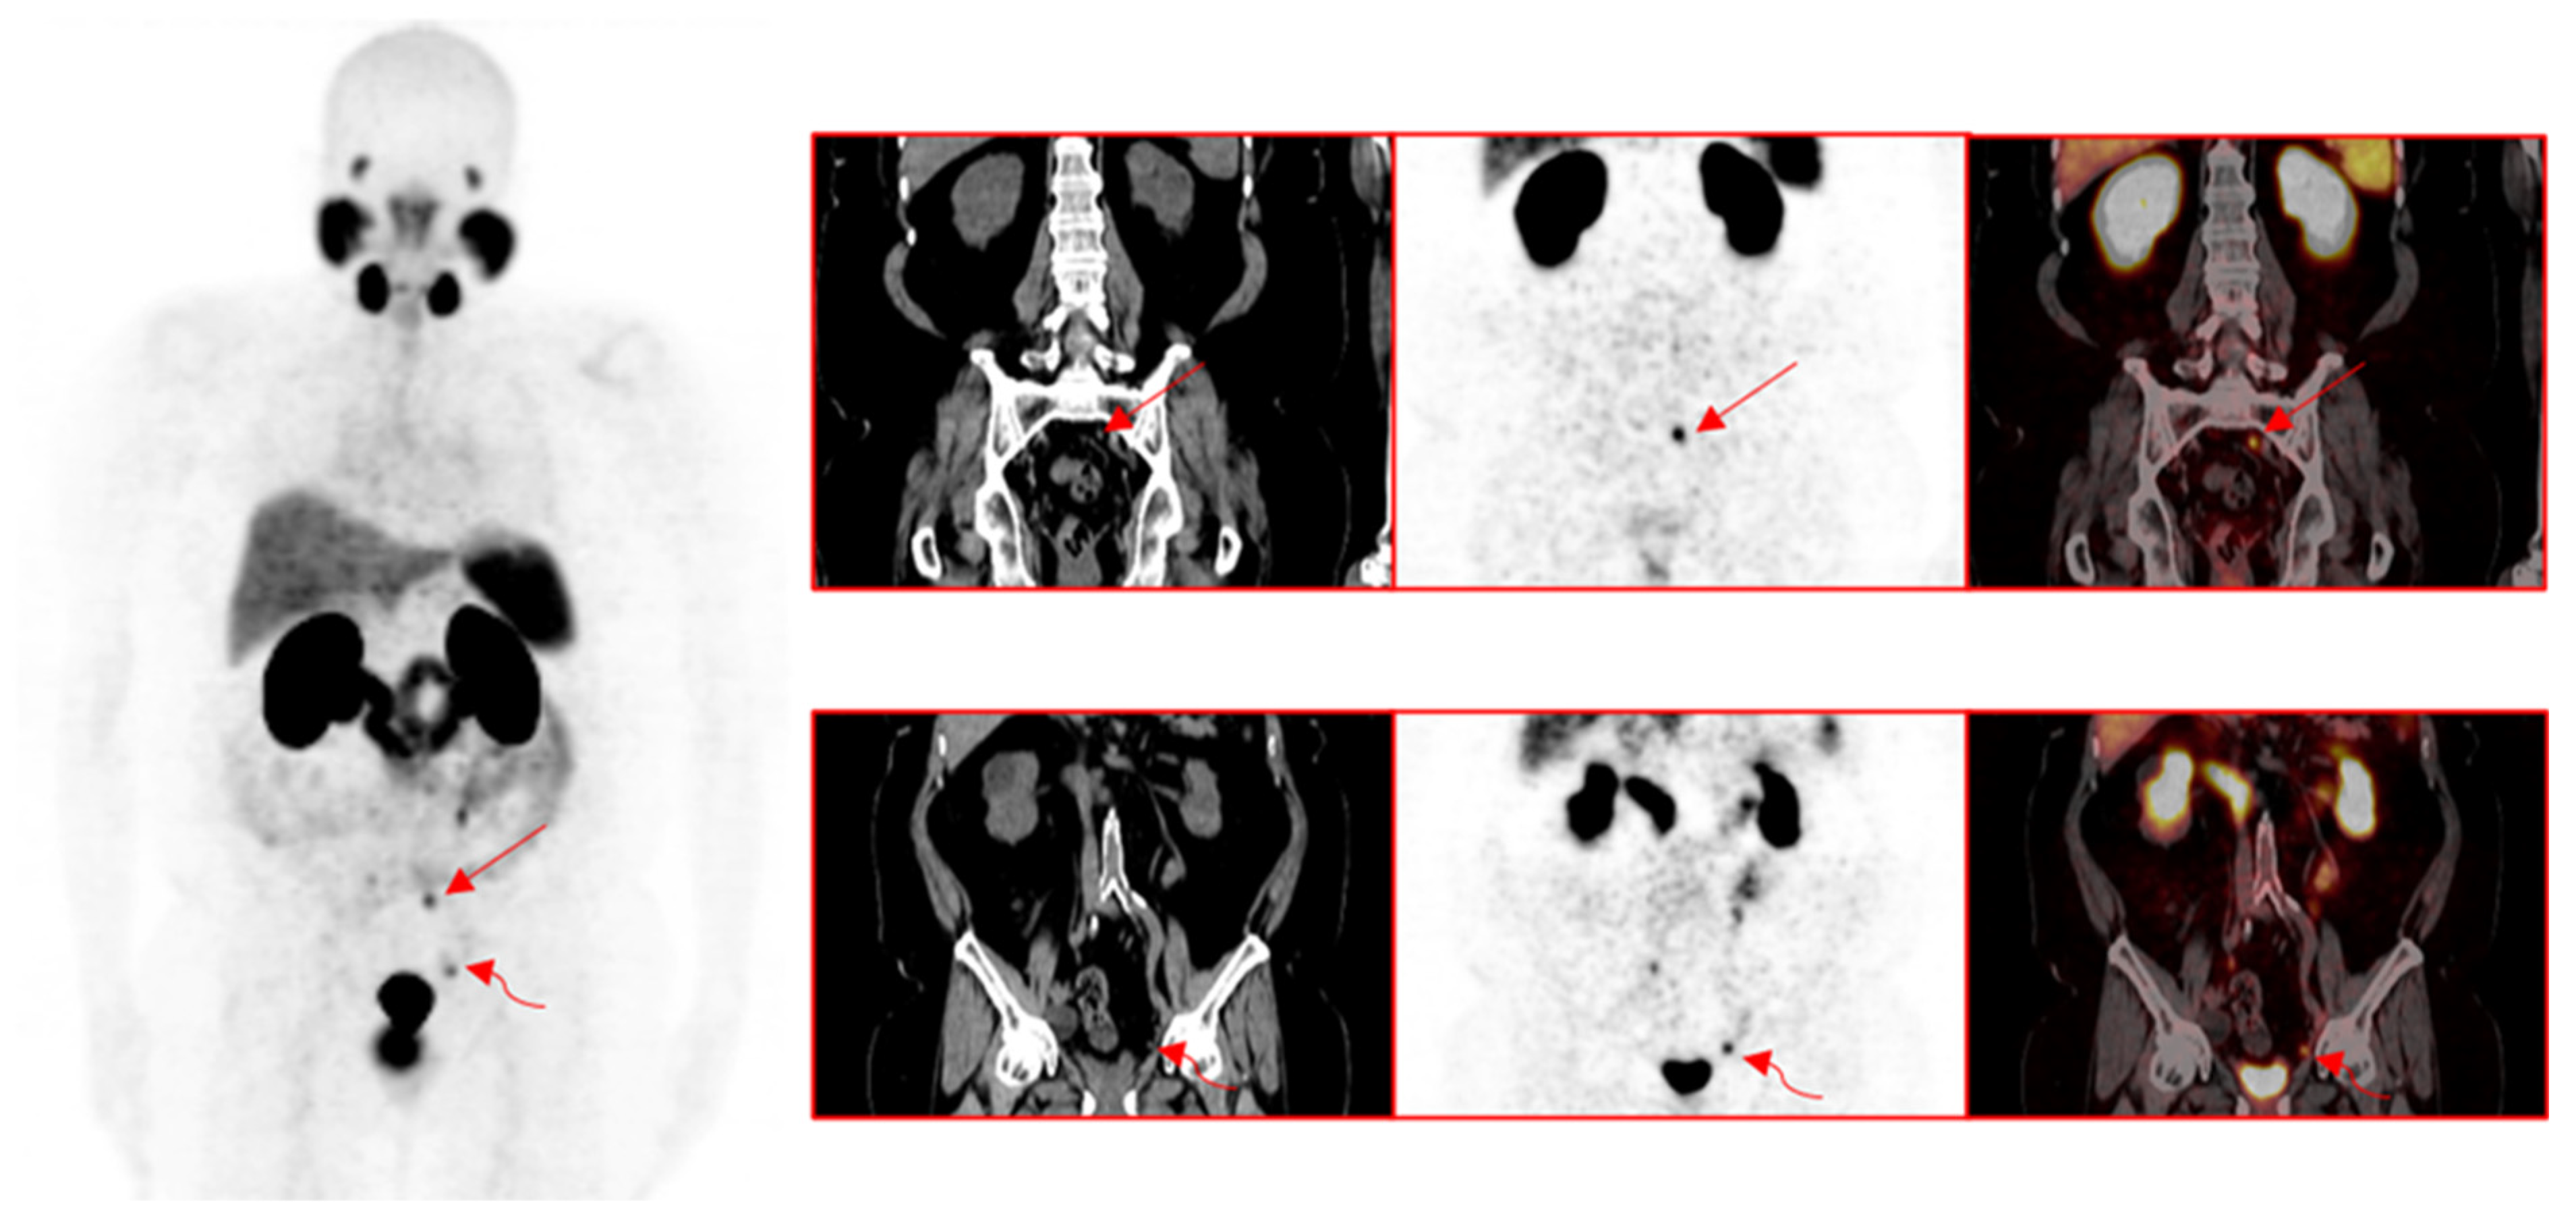

3.1. Pattern of Prostate Cancer Recurrence